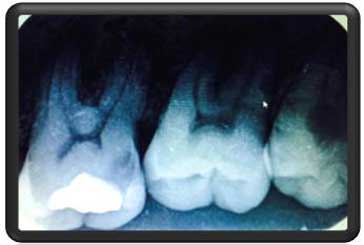

در رادیوگرافی با کیفیت بالا توسط دستگاه دیجیتالی 3disk کمپانی امریکا. پوسیدگی وسیع در محل مشخص شده دیده شد. |